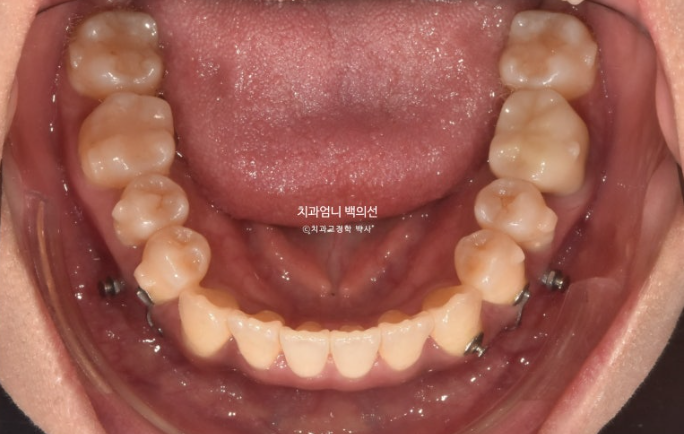

아래는 사랑니가 있던 공간으로 어금니를 뒤로 밀어내어 최종적으로 아래 앞니가 뒤로 2mm 들어가도록 했습니다.

위도 마찬가지로 사랑니 공간으로 어금니들을 전부 후방이동 시켜 덧니가 배열될 공간을 얻기로 했죠.

어금니를 하나씩 뒤로 보내느라 초반 8개월을 대부분 소모합니다. 교정용 나사인 미니스크류도 각 분악당 최소 1개씩은 필요합니다.

아래 앞니가 사랑니 공간을 이용하여 뒤로 2mm 후방이동 했습니다.

앞니 반대교합과 절단교합이 해소가 되며 아랫입술 역시 뒤로 2mm 들어갔습니다.

위 앞니는 목표대로 앞으로 나오지 않게 치료가 잘 되어 윗입술은 변화가 없습니다.